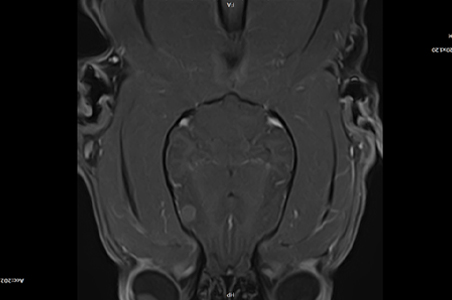

뇌 MRI

선천적인 기형, 뇌수막염, 뇌 출혈, 뇌 경색, 뇌 종양 등